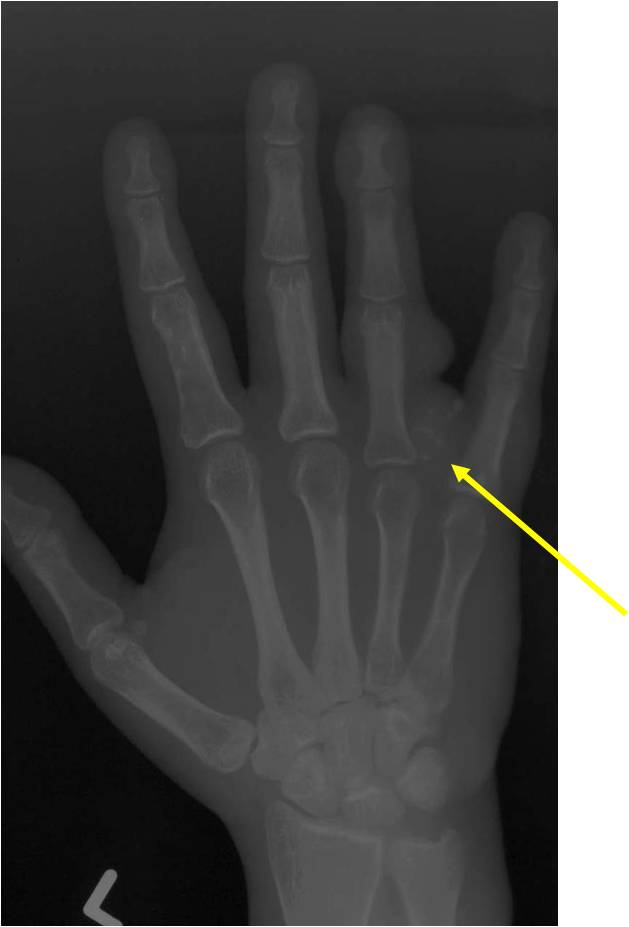

- 50% involve hands and feet (mostly phalanges)

- Cortex may be scalloped and thinned in the phalanges

- Expansile remodeling with thinned cortex

- Endosteal scalloping and cortical expansion is acceptable for phalangeal tumors. In most benign long bone cartilage tumors there is minimal endosteal scalloping but there should be no cortical expansion nor thickening. There should be no cortical destruction and no soft tissue component associated with an enchondroma. Cortical destruction, periosteal thickening, cortical expansion and a soft tissue component indicates a chondrosarcoma of the long bone.

- Enchondromas of digits can have hypercellularity, bi and trinucleated cells and myxoid change and still be considered benign

- Digits: Impending or actual pathological fracture

- Intralesional curettage and bone graft or cement